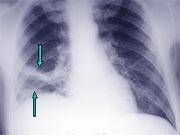

- 多项选择题患者男,突发胸部疼痛, 进行性呼吸困难1小时,行X线片检查, 提示右下肺病变,急诊CT平扫加增强, 如图所示 ( )

A、X线片示右下肺实变影

B、SCT增强扫描示右侧肺动脉主干完全性充盈缺损

C、右肺动脉开口处见不规则软组织密度影

D、考虑为右侧肺动脉(中央性)栓塞